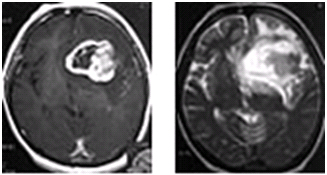

星細胞腫グレードIV(膠芽腫)

グリオーマの大部分を占める組織型で、悪性度は比較的良性のグレード1から最悪性型のグレード4(グリオブラストーマ)に分類されています。悪性度の低いアストロサイトーマでも緩徐進行性で、再発するたびに悪性度を増していくのが一般的です。

一般的に、手術、放射線治療、化学療法などを組み合わせた治療が行われます。グリオーマは悪性度によらず、MRIなどで描出される領域を超えて正常脳に浸潤する形で発育していきます。さらに脳組織は部位により重要な働きが局在(機能局在)しているため、手術による腫瘍細胞の全摘出は多くの場合不可能です。したがって、残存した腫瘍細胞に対する適切な対処が必要となります。多くの場合選択肢となるのは放射線治療と化学療法ですが、グリオーマ細胞は放射線感受性や抗癌剤感受性が一般的に低いと考えられています。